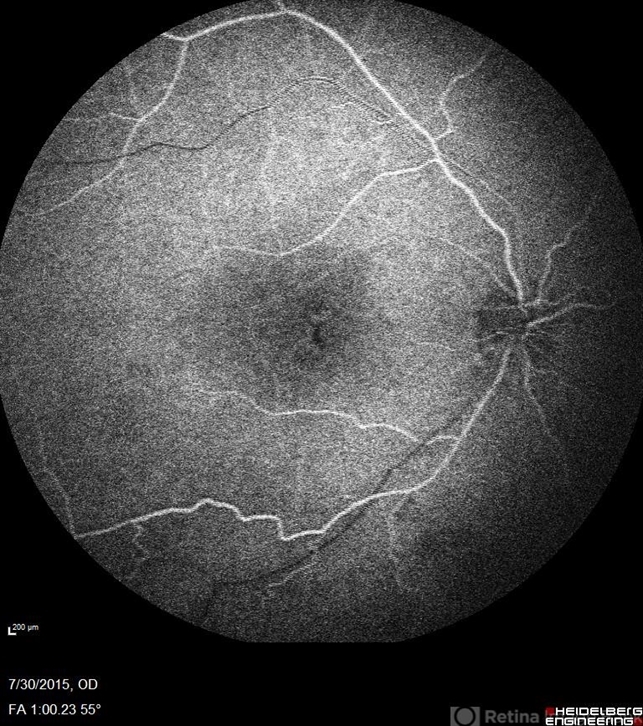

- Goldmann-Favre Syndrome, juvenile retinoschisis, retinal dystrophy

- Fluorescein angiography of a 24-year-old male. Juvenile retinoschisis on OCT. FA shows outer retinal staining. Could be associated with Goldmann Farve Syndrome.